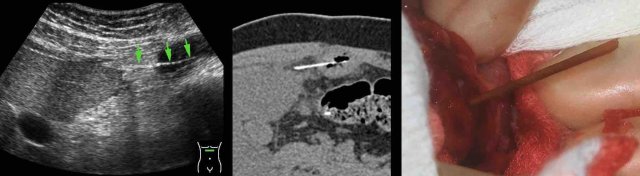

Young (31 years) Surinamese woman with 3 weeks of pain LLQ and CRP 55, suspect for adnexitis or diverticulitis.

Previous history of uterine rupture.

US shows hypoechoic mass left of the uterus (u.) suspect for tubo-ovarian abscess (TOA).

In the periphery a thin, curvilinear reflection (arrows) is seen.

Endovaginal US confirms a fishbone (arrows) in the wall of the TOA.

Non-contrast CT reveals  that the TOA  has a close relation to the sigmoid, which also shows focal wall thickening.

At surgery, TOA  and fishbone, densely adhered to the sigmoid, were removed.

Apparently, the fishbone, after perforating the sigmoid, migrated into the left ovary, causing a TOA.

Note the greenish discoloration of the fishbone, probably due to biliary pigments.